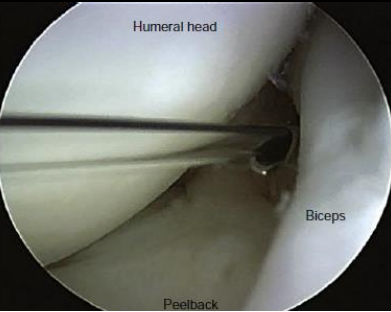

• Como é realizado o “pell-back test” (Burkhart) no diagnóstico atroscópico?

A

• Braço em 90° de abdução + RE de 90°

• O labrum desloca medial no colo da escápula ao realizar RE

• Avalia a extensão posterior da lesão

Reproduz o mecanismo de trauma de movimento de arremesso